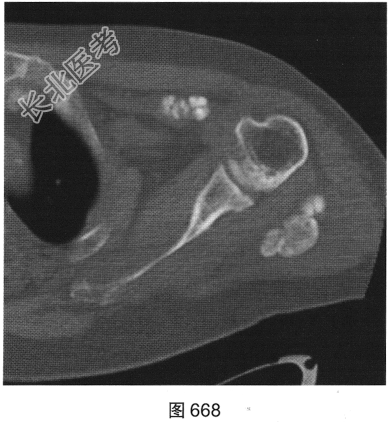

患者男性,33岁。肾衰,透析3年。右髋关节正位X线平片及左肩关节CT见图667、图668。

- 多项选择题2.[提示]患者实验室检查:肌酐334μmol/L(正常值40~135μmol/L), 血磷1.79mmol/L(正常值0.8~1.5),血钙2.34mmol/L(正常值2.1~2.7), 甲状旁腺素4617pg/ml(正常值15~85)。结合上述X线和CT表现,患者应诊断为( )